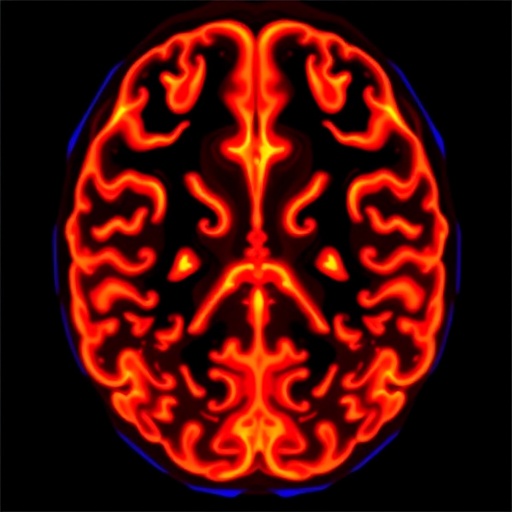

The method’s technical ingenuity lies in the comprehensive analysis of longitudinal MRI data. By comparing sequential scans, the research team generates sophisticated tissue compression maps, revealing how the tumor exerts physical pressure and infiltrates into healthy regions. These biomechanical maps are not simple visualizations but quantifiable signatures that provide a deeper understanding of the tumor’s biomechanical footprint within the neural landscape, enabling precise characterization that transcends volumetric assessments.

From a technical standpoint, the DIR calculation involves sophisticated image registration techniques and biomechanical modeling to quantify tissue deformation. It integrates the tumor’s volumetric changes with spatial patterns of tissue compression, thus providing a composite index that encapsulates the infiltration dynamics and mechanical mass effects. This integrative model represents a significant innovation in neuroimaging analytics.